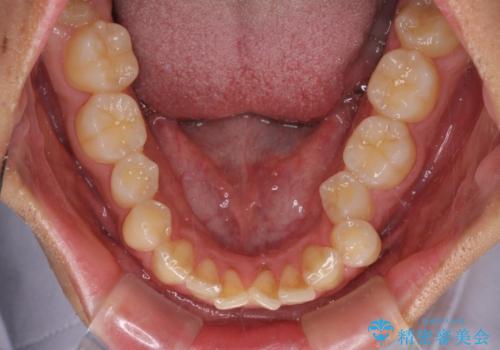

捻れて飛び出した前歯 インビザラインで整った前歯に

- 上下前歯のデコボコと、それに伴う出っ歯を気にして来院された患者様です。

インビザラインによる上下歯列の側方拡大と後方移動、IPR(歯と歯の間を削る)にるスペースの獲得により歯列を整えることとしました。